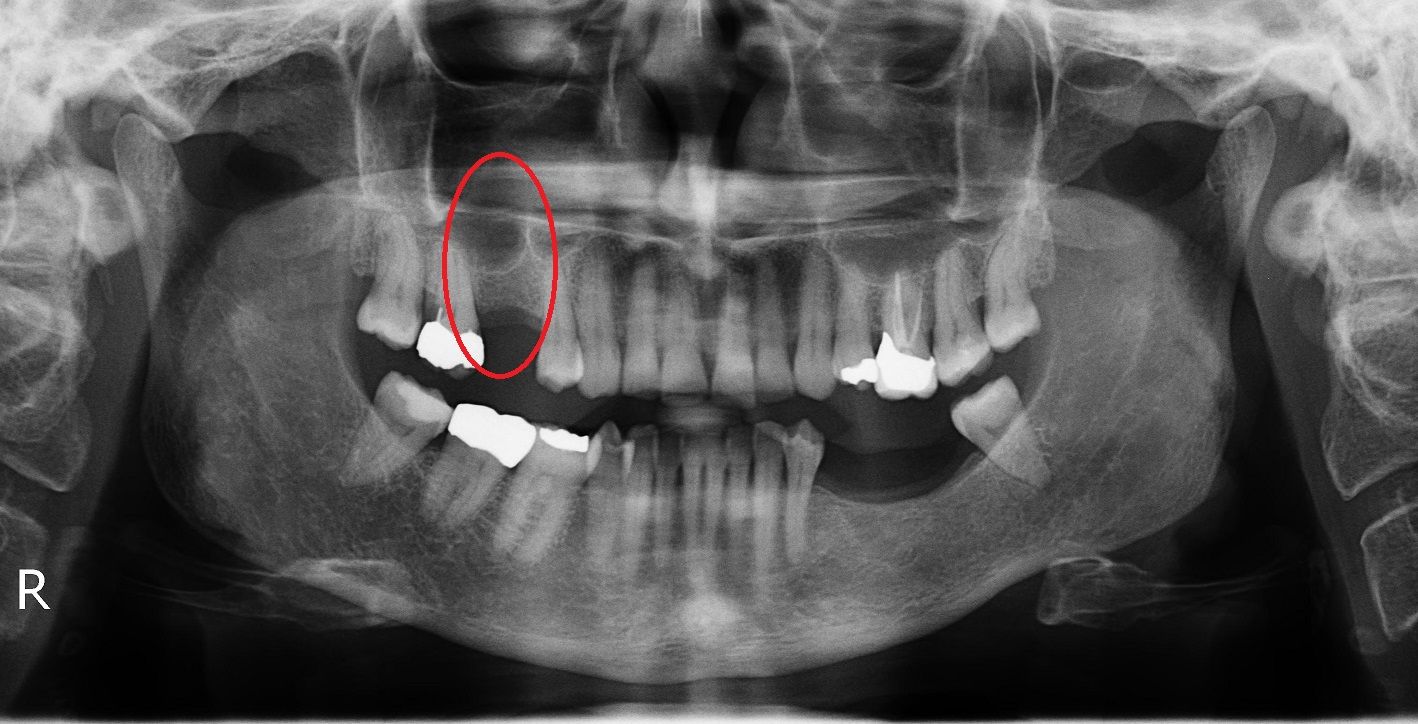

Синус лифтинг

После удаления зуба из-за отсутствия необходимой нагрузки на челюсть, кость в пустующем месте атрофируется. В этом случае перед имплантацией необходимо восполнить объем костной ткани.

Разновидность костной пластики направленной на увеличение объема костной ткани верхней челюсти в районе гайморовых пазух.

Открытый синус лифтинг

Открытый синус-лифтинг применяется, когда для установки имплантата не хватает более 3 мм костной ткани. При проведении этой операции имплантация в ряде случаев возможна только после полного восстановления кости челюсти.

Закрытый синус лифтинг

Закрытый синус-лифтинг подходит для наращивания небольшого объема костной ткани (1-3 мм). Он менее травматичен, чем открытый. Подсадка костного материала проводится через небольшое отверстие для имплантата.

При закрытом типе синус-лифтинга имплантация проводится сразу. Вам не придётся лишний раз посещать стоматолога.

• до синус-лифтинга

• после синус-лифтинга

• после установки имплантатов в верхнюю челюсть